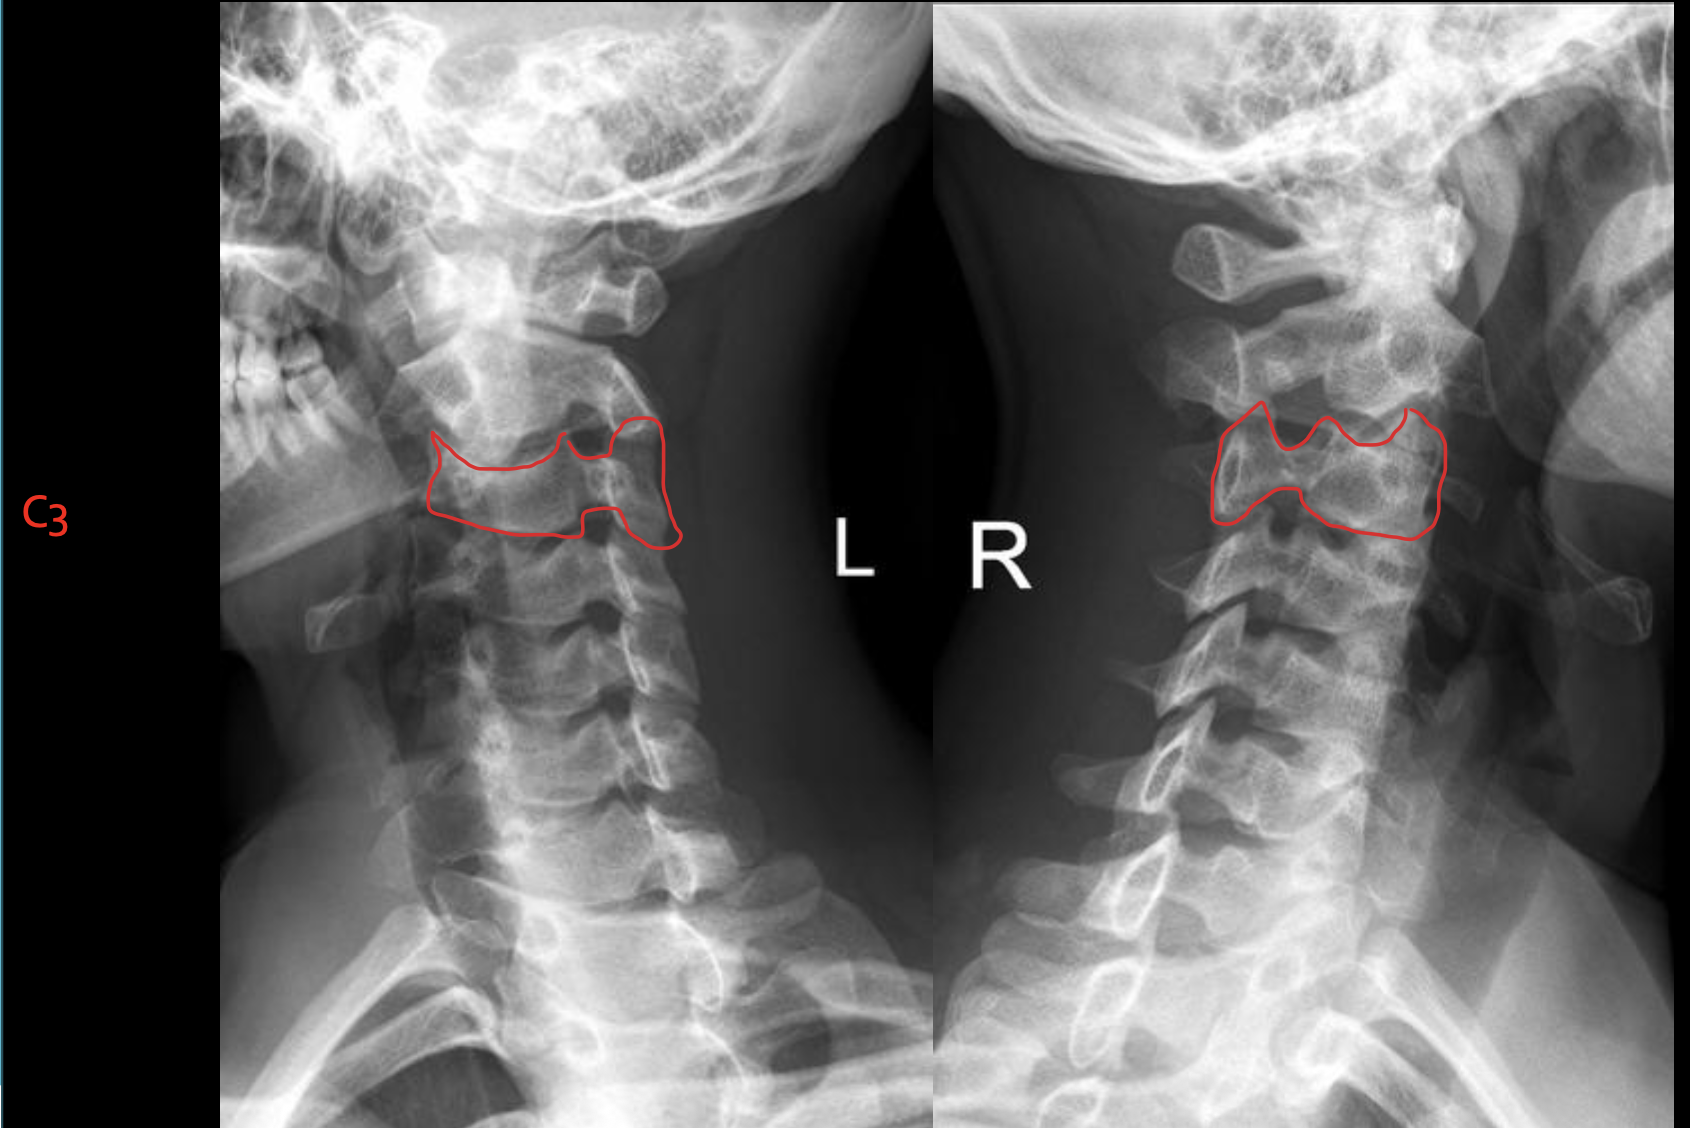

C3